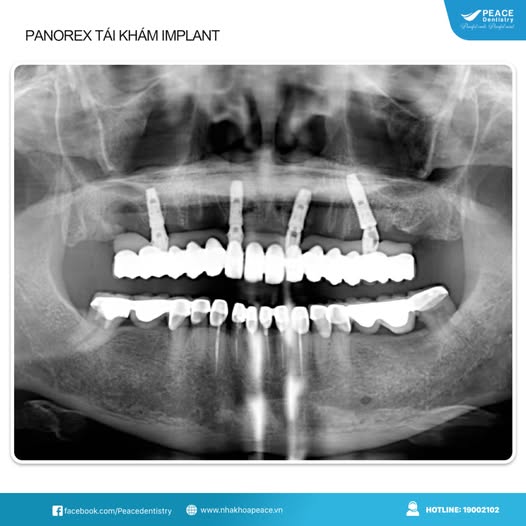

(Hình ảnh Panorex của khách hàng tái khám sau khi trồng implant 5 năm)(**)

(Hình ảnh Panorex của khách hàng tái khám sau khi trồng implant 6 năm)(**)